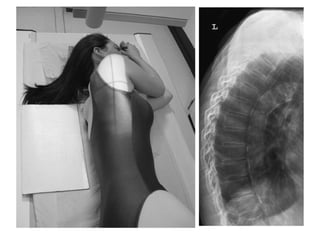

Thoracic Spine-Lateral

Position

• Make the patient to lie or stand in front of the x-ray table in

lateral position.

• Mid saggital plane should be parallel to the center of the

table.

• Arm should be raised well above the head.

• The head can be supported by pillow & pads may be placed

between the knee for the patients comfort.

• Radiation Production given to the patient.

Tube Centering

• The tube center at the level of 1" below the axila T7 & T8.

Cassette centering

• The upper border of the cassette is kept 3 to 4 cm above the

spinous process of the C7.

Exposure Settings

Distance Focal Spot Grid kV mAs

Tube

Angulation

Cassette

Size

100 cm Large Yes 65-70 100-120 0° 12"X15"